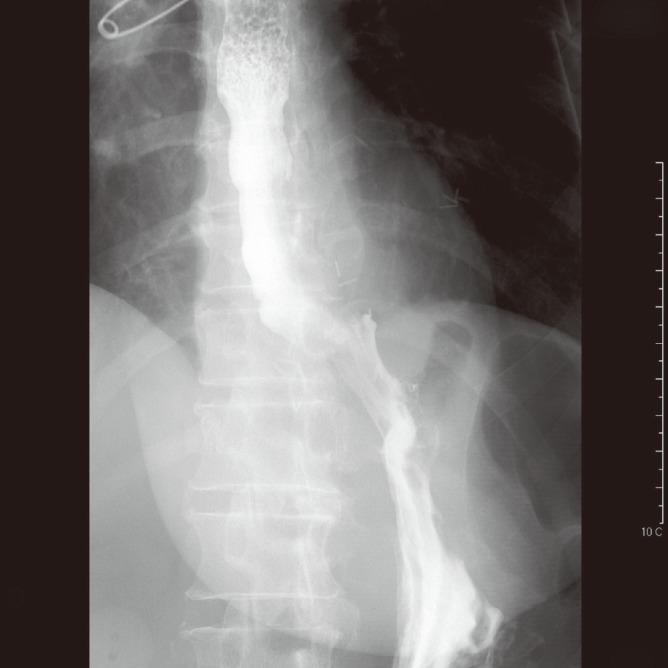

Gastroplasty for esophageal perforation after endoscopic balloon dilatation for achalasia: two cases.

Complete endoscopic closure (clipping) of a large esophageal perforation after pneumatic dilation in a patient with achalasia.

Surgical repair of esophageal perforation due to pneumatic dilatation for achalasia. Is myotomy really necessary?

Management of esophageal perforation after pneumatic dilation for achalasia.

Conservative management of esophageal perforations during pneumatic dilation for idiopathic esophageal achalasia.